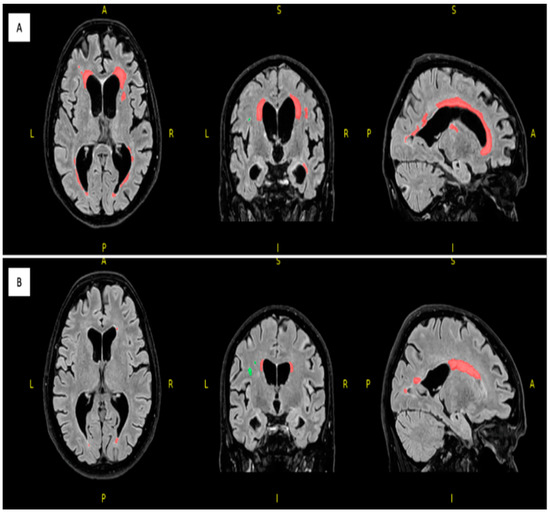

For white matter hyperintensity analysis, we used the volBrain’s DeepLesionBrain (DLB) pipeline (https://www.volbrain.upv.es (accessed on 8 February 2023)). VolBrain is an MRI brain volumetry software that operates automatically and can offer brain structure volumes without human involvement; it was developed by José V. Manjón (IBIME, UPV, Valencia, Spain) and Pierrick Coupé (LaBRI UMR 5800, Université de Bordeaux, CNRS, Bordeaux, France). VolBrain employs an entirely automated pipeline for volumetric brain analysis based on multi-atlas label fusion technology, which can provide accurate volumetric information at various levels of detail in a short time [25]. WMH segmentation starts with image denoising, which is followed by inhomogeneity correction, spatial registration, intensity normalization, and intracranial cavity extraction by employing the Montreal Neurological Institute algorithm (MNI). The tissue is then segmented using a multi-template fusion atlas strategy, originating from a library that was produced by manually segmenting 43 patients by an expert radiologist using multimodal MRI data. Voxels surpassing a specific threshold are lesion candidates; the volBrain program automatically handles thresholding and voxel processing. The identified lesions are allocated into four anatomical regions: paraventricular, deep white, juxtacortical, and infratentorial, which are further divided into cerebellar and medullar regions. The number, volume, and distribution of each lesion are recorded. The process concludes with the generation of an automated report containing the lesion load, number of lesions per class, and screenshots of the processed images. Additionally, DLB provides the probability of disconnection caused by the detected lesions for 64 white matter tracts and estimates a disconnectome map based on the HCP1065 atlas [26]. Figure 1, Figure 2 and Figure 3 demonstrate MRI FLAIR sequence segmentation using volBrain DLB.

Figure 1.

Segmented FLAIR MRI imaging of the 77 years old female monozygotic twin pair in 2022 using DLB (axial, coronal and sagittal planes); the affected twin (A) has a total number of 36 WMHs (first row) and the unaffected twin (B) has a total number of 36 WMHs (second row). Red represents the periventricular WMH and green shows the deep white matter WMH; image from the Semmelweis University Medical Imaging Centre. A: anterior; P: posterior; L: left; R: right.

Concerning neuroimaging, we detected a left cerebellar lacunar stroke and signs of PSP (midbrain atrophy) in the affected twin; signs of normal-pressure hydrocephalus (NPH) were also observed. However, the latest brain MRI certified questionable signs of a possible beginner PSP, a narrow oedematous signal disorder in the cerebellar tonsils, and possible signs of normal-pressure hydrocephalus in the unaffected twin (Figure 1 and Figure 2).

Based on the DLB analysis using the HCP1065 atlas, out of the 64 analyzed white matter tracts in the affected twin pair, 60 tracts were affected by lesions (disconnection probability of above 55%), excluding left and right fornices and the cingulum parahippocampal tracts. On the other hand, in the unaffected twin pair, more than 33% of the analyzed tracts were unaffected by lesions (disconnection probability of 0%).

The white matter hyperintensity analysis using volBrain’s DLB pipeline demonstrated remarkable differences between the twins, especially in the total, periventricular, and juxtacortical WMH lesion volume, which were higher in the affected twin (Table 4).